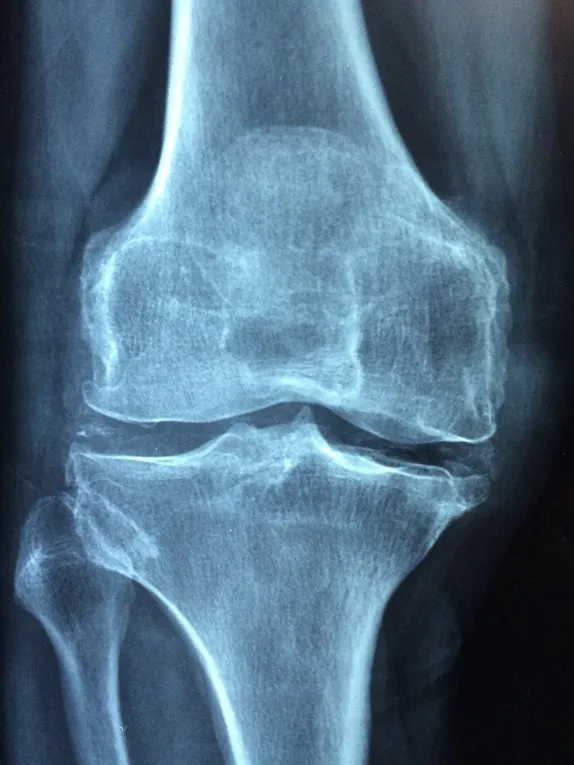

Knee X-ray

At Swank Chiropractic Sports Medicine, our doctors use an integrated sports medicine model to restore knee function—not just manage symptoms.